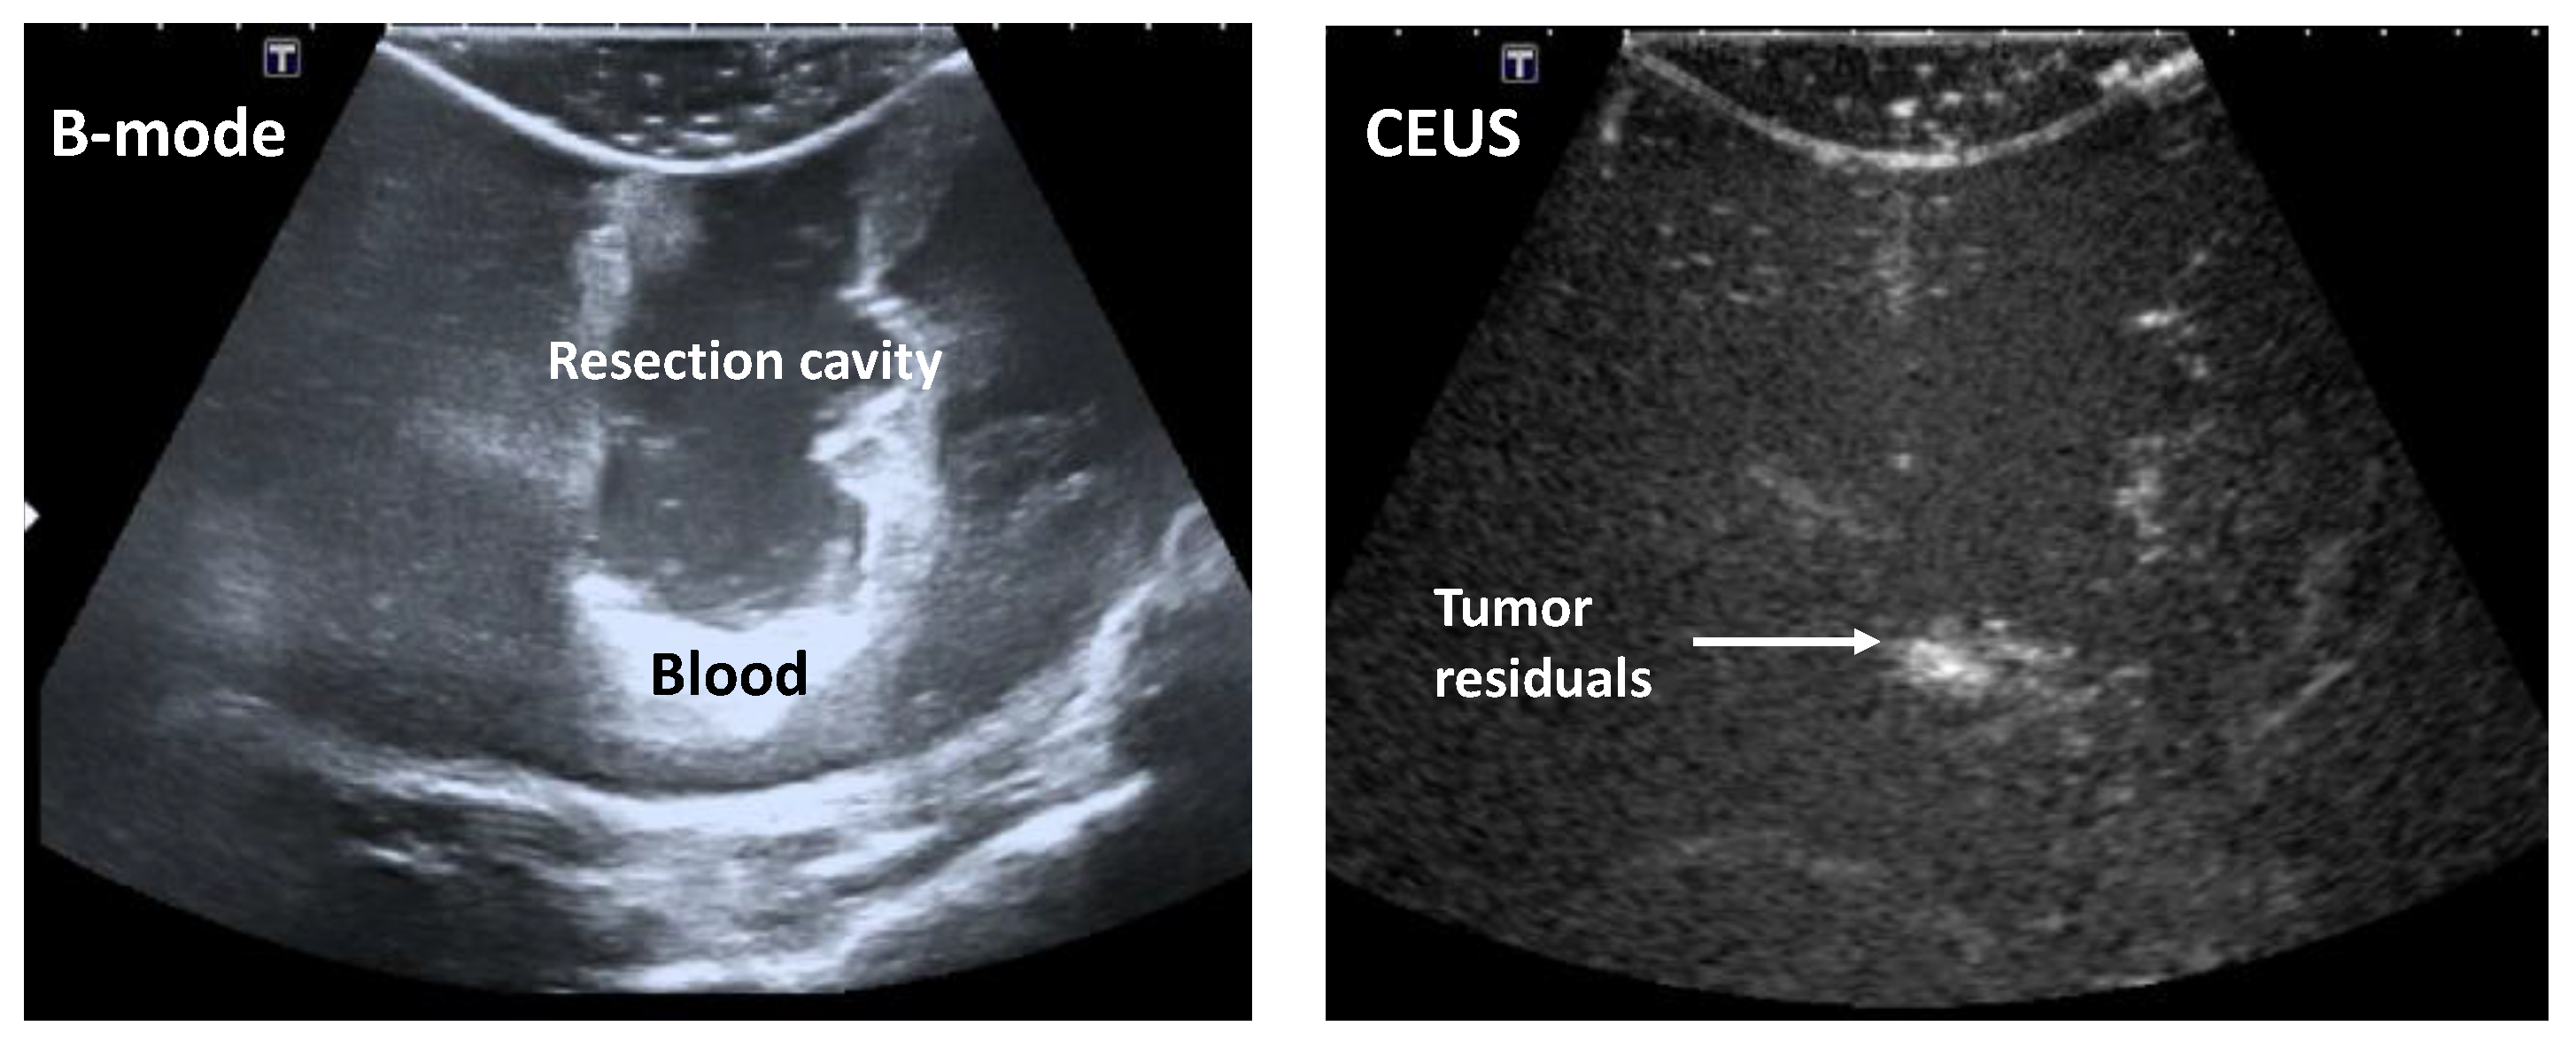

However, the identification of tumor residuals in the iUS data remains in general complex for the expert-eye. Depending on the position of the tumor within the patient’s head, the resection cavity, as well as other cerebral structures like blood vessels, potentially ventricles and bone structures, are usually well depicted in the iB-mode image data. However, the possible tumor residuals are hardly differentiable from other hyperechogenic structures, like the border of the resection cavity, blood or artifacts (Figure 2, left). Furthermore, it is only attempted to enhance the blood vessels and vascularized structures, like tumors, in the iCEUS image data. Furthermore, the borders of the resection cavity, which are important structures that are needed to analyze the images correctly, are hardly or not at all visible (Figure 2, right). The combination of the information in the iB-mode and iCEUS image data, also called data fusion, can support the identification of tumor residuals.

Figure 2.

Intraoperative B-mode ultrasound (iB-mode) (left) and iCEUS (contrast enhanced ultrasound (CEUS)) (right) patient image data acquired at the end of a brain tumor operation.